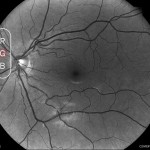

ステレオビューアテクノロジー

DRSplus ステレオビューアは、自動的に鼻側の異なる角度と異なる焦点面で(二重焦点)、2つの別々の写真を撮影し、視神経乳頭部の3D画像化を可能にします。

※ステレオビューアはオプション機能です。